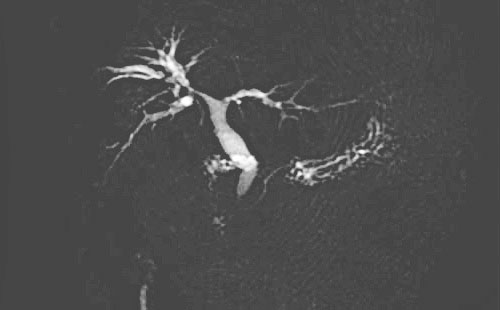

2)胸部CT:右侧胸腔积液,较前明显好转;右侧少许感染(图9)。

图9 术后MRCP

3)复查MRCP肝内胆管无结石残留(图10)。

图10 术后胸部CT